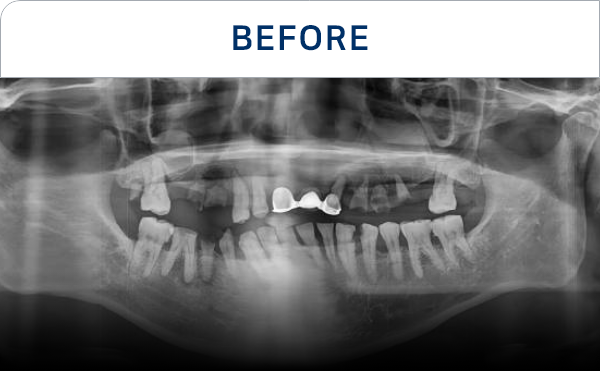

种植牙是在精准诊断与治疗计划的基础上,

通过多个步骤进行的治疗方式

会根据患者的口腔状况, 分阶段安全推进

准确掌握口腔状况

了解所需的治疗方向

通过CT, 扫描等数字设

备拍摄后,

进行精密分析

考虑骨骼状态与神经位置,

制定种植位置与手术计划

根据患者状况,

应用个性化种植牙设计